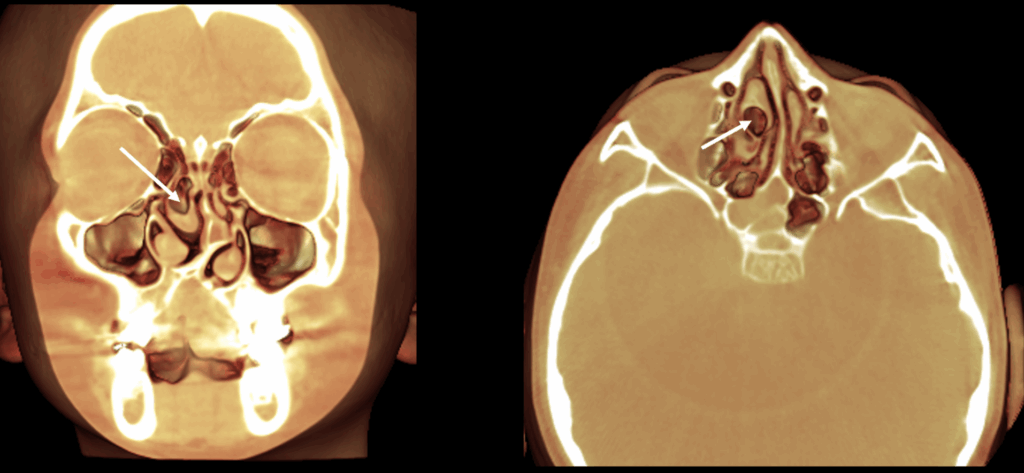

A la evaluación de la tomografía volumétrica (cone beam) de macizo facial en los cortes coronales (Figura 2), axiales y sagital (Figura 3) se observa el defecto óseo que se extiende desde la cima del reborde alveolar hasta el piso de la fosa nasal del lado izquierdo comprometiendo ambas estructuras, desviación del tabique hacia lado izquierdo y neumatización del cornete medio de lado

derecho,

CORTES CORONALES

En la reconstrucción 3D de tejidos blandos se observa la fisura alveolo palatanila unilateral y la presencia de concha bullosa de cornete medio de lado derecho

RECONSTRUCCIÓN 3D